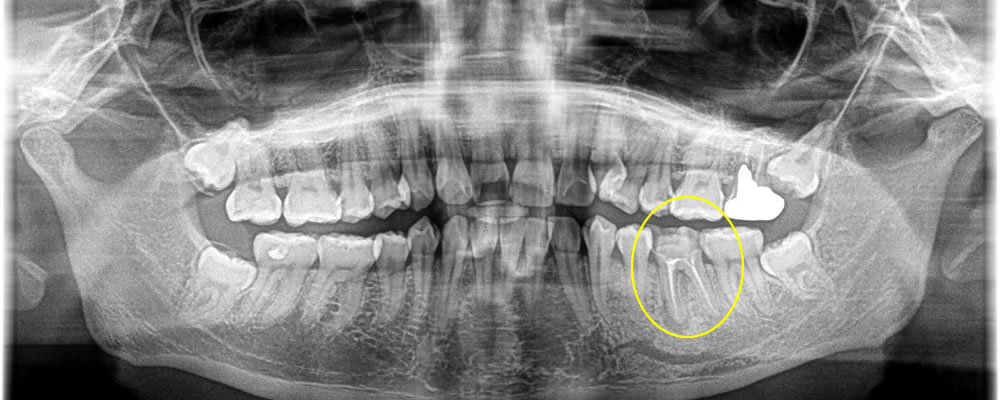

膿が溜まった歯を抜歯後にインプラントで治療した症例

年齢

30代

性別

男性

症例を見る